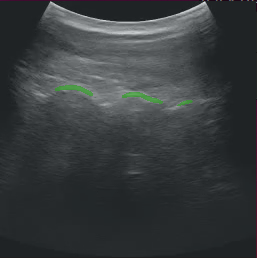

按照上述指示修改应用程序后,运行该应用程序应显示带有分割掩码叠加层的超声视频,类似于下图。

app_ultrasound.png

图 11 超声分割